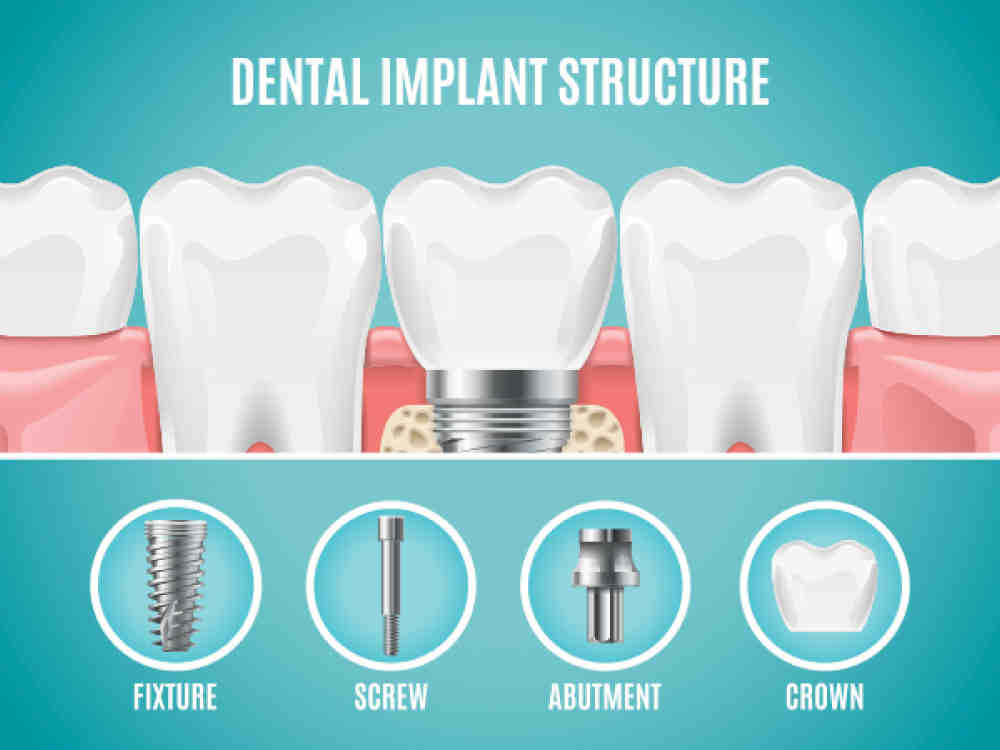

As mentioned above, the dental implant or the “ dental root ” of this procedure, it can be between $ 1,000 and $ 3,000. But the dental implant is only one piece of the cake. Other costs that should be considered are the abutment which is usually between $ 300 and $ 500 and the crown which is usually between $ 1,000 and $ 2,000.

The cost for a single dental implant in California is estimated to be between $ 3,000 and $ 4,500; according to the New York Times and the American Academy of Implant Dentistry. This cost includes one implant, one abutment and the crown of the implant. On the same subject : Can dental implants be removed. This can be expensive and dental insurance can help pay for the implant crown.